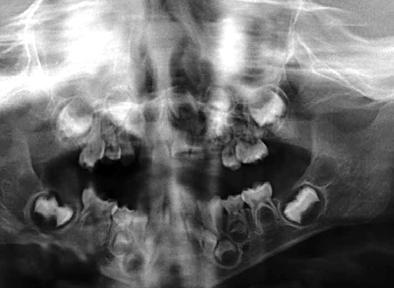

Figura 2. A. Radiografía periapical donde se observa la lesión del odontoma compuesto a nivel del maxilar superior izquierdo. B. Ortopantomografía que revela una lesión radiolúcida unilocular bien definida, con manchas de focos radiopacos, asociada con el canino superior izquierdo temporal impactado de la maxila.

El examen clínico reveló un aumento de volumen en la zona de órganos dentarios 63-65 que se extendía al seno maxilar, con desplazamiento de cortical vestibular, sin perforación ni cambio de color en la mucosa, de estructura uniforme bien delimitada. (Figura 1). En el examen radiográfico se observó la expansión de la cortical, con la presencia de múltiples dentículos. Desplazamiento del órgano

dentario 63 hacia el seno maxilar (Figura 2).

Radiográficamente estas lesiones presentan un área radiolúcida bien definida que contiene cantidades variables de material radiopaco de irregular tamaño y forma. La extensión de las áreas radiopacas y radiolúcidas difieren de una lesión a otra, dificultando muchas veces su diagnóstico radiológico en ocasiones la

cantidad de material mineralizado predomina semejando un odontoma complejo. El tumor puede producir una expansión variable de las corticales y encontrarse asociado a una pieza retenida, a la cual puede desplazar o interferir en su erupción.13